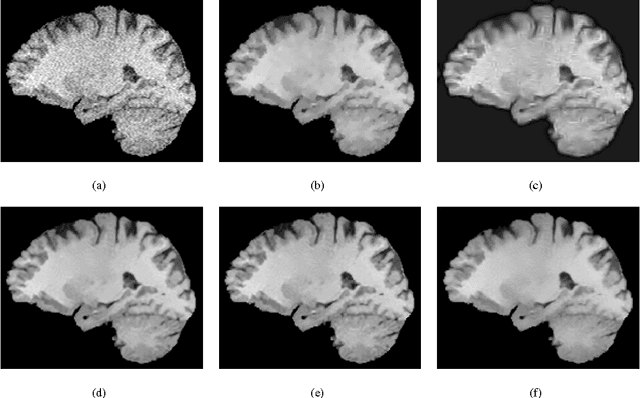

Abstract:The acquisition of MRI images offers a trade-off in terms of acquisition time, spatial/temporal resolution and signal-to-noise ratio (SNR). Thus, for instance, increasing the time efficiency of MRI often comes at the expense of reduced SNR. This, in turn, necessitates the use of post-processing tools for noise rejection, which makes image de-noising an indispensable component of computer assistance diagnosis. In the field of MRI, a multitude of image de-noising methods have been proposed hitherto. In this paper, the application of a particular class of de-noising algorithms - known as non-local mean (NLM) filters - is investigated. Such filters have been recently applied for MRI data enhancement and they have been shown to provide more accurate results as compared to many alternative de-noising algorithms. Unfortunately, virtually all existing methods for NLM filtering have been derived under the assumption of additive white Gaussian (AWG) noise contamination. Since this assumption is known to fail at low values of SNR, an alternative formulation of NLM filtering is required, which would take into consideration the correct Rician statistics of MRI noise. Accordingly, the contribution of the present paper is two-fold. First, it points out some principal disadvantages of the earlier methods of NLM filtering of MRI images and suggests means to rectify them. Second, the paper introduces a new similarity measure for NLM filtering of MRI Images, which is derived under bona fide statistical assumptions and results in more accurate reconstruction of MR scans as compared to alternative NLM approaches. Finally, the utility and viability of the proposed method is demonstrated through a series of numerical experiments using both in silico and in vivo MRI data.